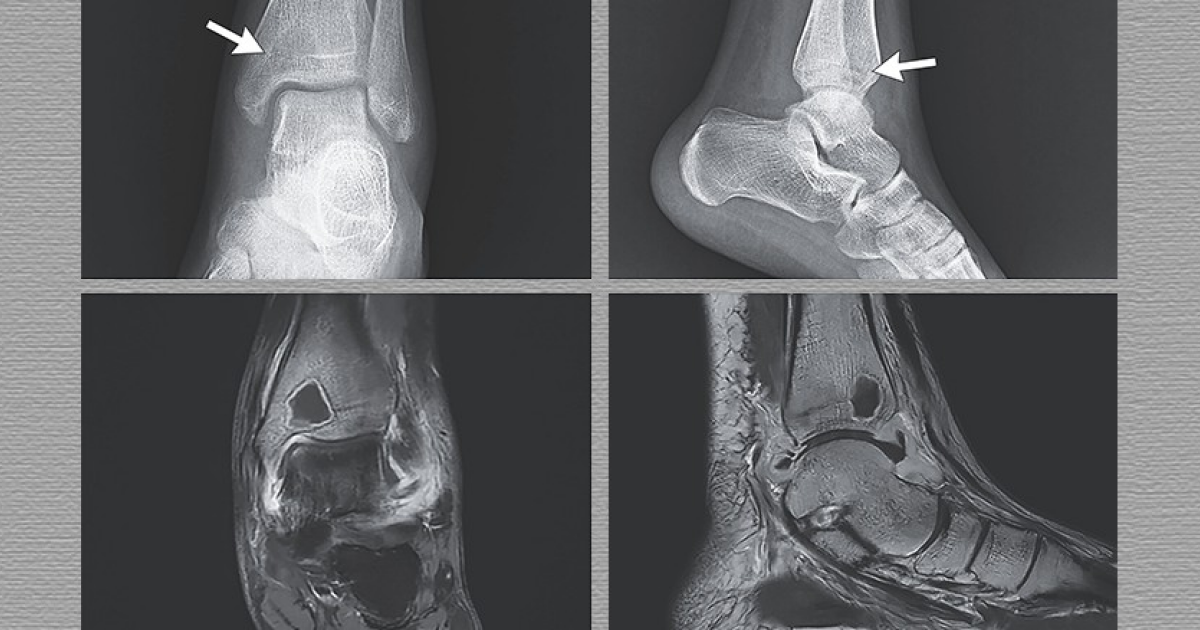

В китайскую ортопедическую клинику поступила прежде здоровая 16-летняя девушка с жалобами на боль в левой лодыжке в течение месяца и повышенную температуру тела в течение 11 дней. При осмотре определялась чувствительность при пальпации левой лодыжки и ограничение активного и пассивного объема движений в ней. На рентгенограмме было видно рентгенопрозрачное образование с нечеткими краями, перекрывающее зону роста в дистальной части большеберцовой кости, а также отек мягких тканей без признаков перелома или реакции надкостницы. Врачи Хайцзянь Ли (Haijian Li) и Пей Хань (Pei Han) из аффилированной...